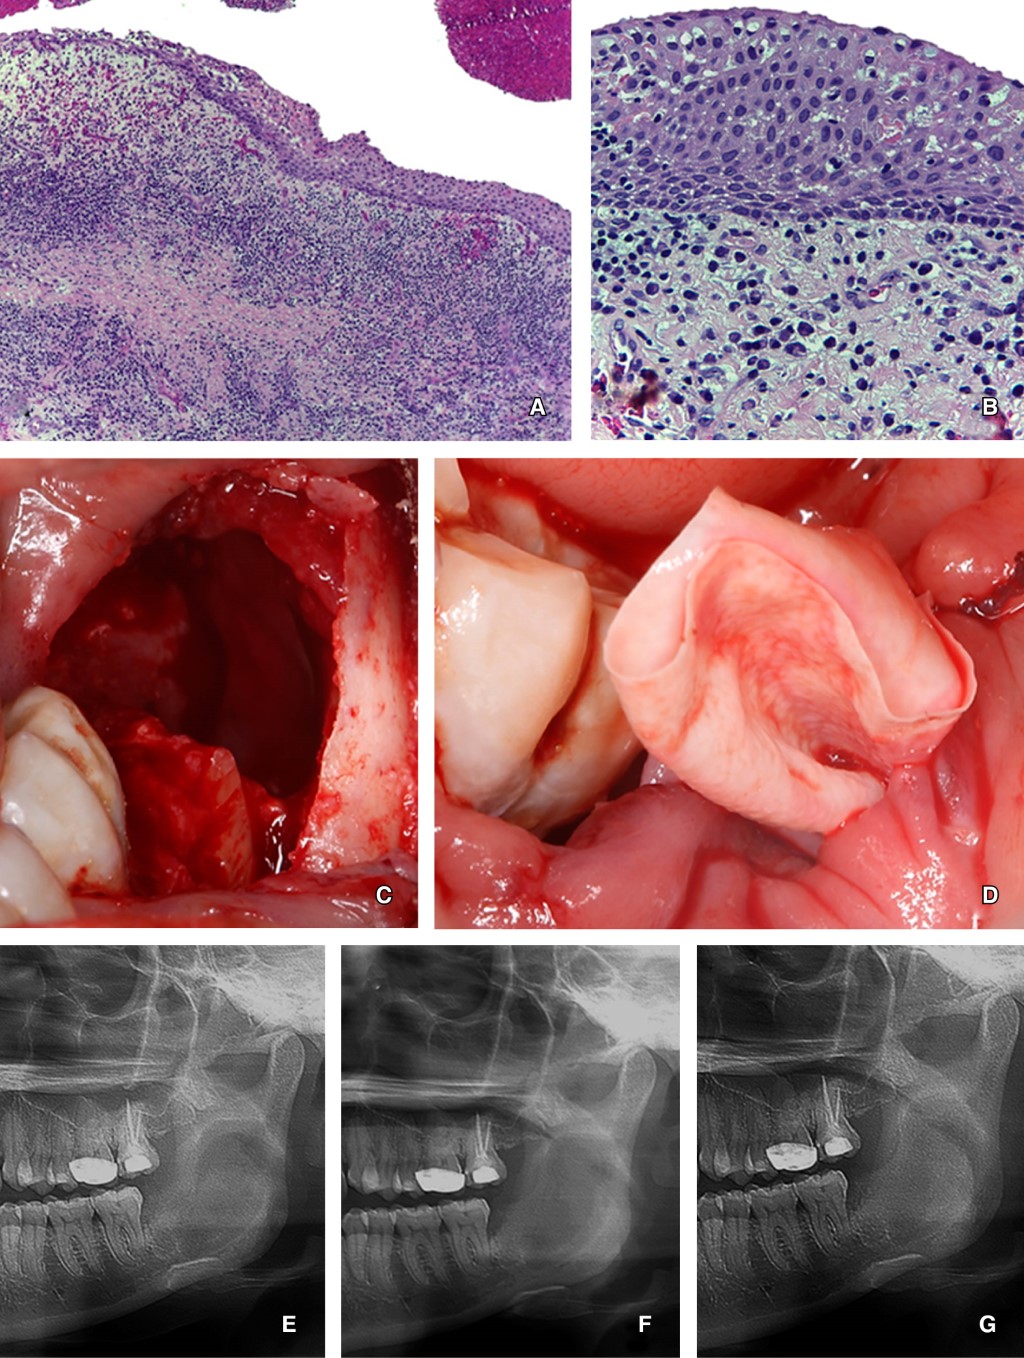

El estudio histopatológico reveló una cavidad revestida por epitelio plano estratificado, con algunas zonas del estrato basal en empalizada, hipercrómaticas y otras con acantosis, exocitosis leucocitaria y áreas con hiperplasia arcoidal. Sin embargo, debido al severo infiltrado inflamatorio, las características distintivas del KC odontogénico se encontraban modificadas: la cápsula del tejido conjuntivo fibroso denso y bien vascularizado, también presentaba un infiltrado inflamatorio crónico linfoplasmocitario severo y difuso, con calcificaciones distróficas, cementículos y matriz osteoide. Por último, se emitió el diagnóstico de queratoquiste odontogénico con proceso inflamatorio crónico (Figura 2 A y B).

Procedimiento quirúrgico: el tratamiento consistió en realizar la descompresión de la lesión quística, seguida de marsupialización y enucleación con osteotomía controlada. Primero, bajo anestesia local se realizó una incisión en el borde anterior de la rama mandibular y se extendió hasta el segundo molar; en seguida, se realizó la extracción de los fragmentos del órgano dentario 38. A continuación, se observó una perforación de la cortical vestibular, y en esta zona se accesó a la luz del quiste y se colocó un tubo de látex tipo penrose, el cual fue suturado a la mucosa sana adyacente para dar seguimiento a la marsupialización (Figura 2 C y D). Finalmente, se realizaron lavados quirúrgicos con solución fisiológica.

Una vez concluido el procedimiento quirúrgico se le indicó a la paciente que irrigara y permeabilizara el tubo con clorhexidina al 0.12%, diariamente y dos veces por día. La paciente acudió a un seguimiento radiográfico mensual hasta que se observó un aumento de la radiopacidad de la lesión. Después de cinco meses, la radiografía mostró disminución de la lesión y una zona residual radiolúcida de aproximadamente 1 × 1 cm de diámetro (Figura 2 E-G), aproximadamente 80% menor al tamaño original de la lesión. En este punto se decidió realizar la biopsia excisional de la lesión con osteotomía periférica controlada.